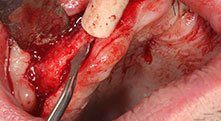

Bratu: Preferimos realizar las osteotomías en la línea oblicua externa de la cara posterior del maxilar inferior, y no en la región situada entre los orificios. Tras realizar una incisión en los tejidos blandos, utilizamos las nuevas sierras para definir el contorno de la osteotomía. De este modo, conseguimos una preparación completa en prácticamente el 80 por ciento de los casos. Por otro lado, en algunas ocasiones también utilizamos otros insertos piezoquirúrgicos, así como un cincel para mover el injerto. Para nosotros, esta es una técnica de intervención muy eficaz.

Bratu: Nos gusta utilizar la técnica de sándwich para realizar aumentos en la cara lateral del maxilar inferior. En este procedimiento, se utiliza la sierra piezoquirúrgica para preparar una tapa ósea, mientras que el fragmento crestal se fija con microtornillos. Entre medias, colocamos una combinación de hueso autólogo y material óseo adicional xenógeno. Y con ello obtenemos un rendimiento muy fiable. Asimismo, en los ranurados de la cresta alveolar del maxilar inferior, nunca se puede prescindir de cortes verticales suficientemente dimensionados, pues, de lo contrario, los huesos pueden fracturarse fácilmente.

Bratu: Considero que la piezocirugía constituye un gran salto hacia delante en cirugía oral. Gracias a esta técnica, las preparaciones óseas resultan más sencillas y ligeras. Además, se pierde menos hueso, por ejemplo, en las extracciones. Este aspecto es muy importante en la zona estética, sobre todo cuando se ha planeado realizar un implante inmediato. Del mismo modo, la piezocirugía también es una apuesta segura para los tejidos blandos. Gracias a ella, las lesiones en la membrana del seno maxilar, así como las lesiones nerviosas cuando se realizan extracciones de injertos óseos, son prácticamente cosa del pasado. También hay datos que demuestran que se producen menos inflamaciones y molestias postoperatorias. Dicho sea de paso, la piezocirugía también permite preparar muy bien los tabiques de los senos maxilares. Y, por supuesto, no hay que olvidar que nuestros pacientes se ven beneficiados por la menor agresividad de esta técnica.